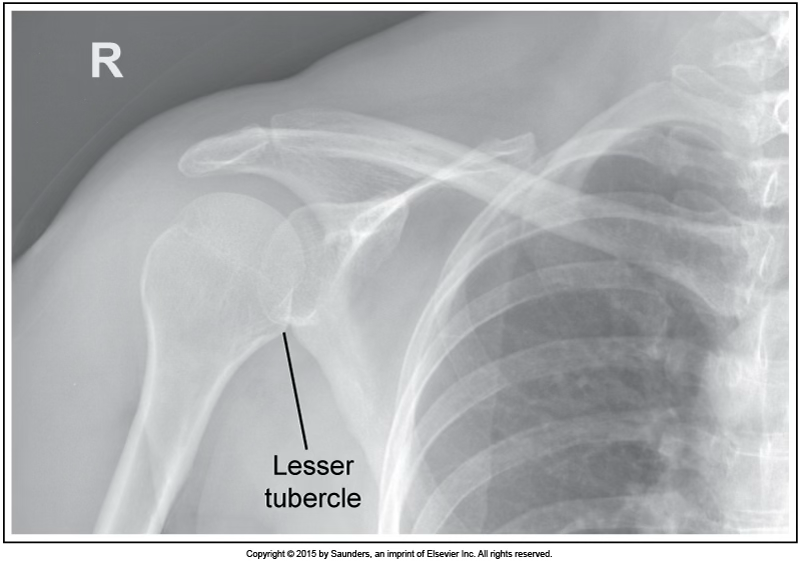

AP neutral shoulder

accurate positioning